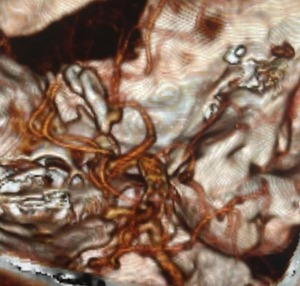

Computed tomography angiography (CTA) revealed an anomalous saccular aneurysm (7×5 mm) arising from the M1 segment of the right middle cerebral artery [Figure 2]. This finding was unusual as the branching artery demonstrated characteristics consistent with orbitofrontal artery territory supply. Digital subtraction angiography (DSA) performed via right femoral approach using a JR 3.5 5F guide catheter confirmed a Type 3 aortic arch with the anomalous aneurysm location [Figure 3]. The aneurysm demonstrated a broad neck and favorable morphology for microsurgical intervention.